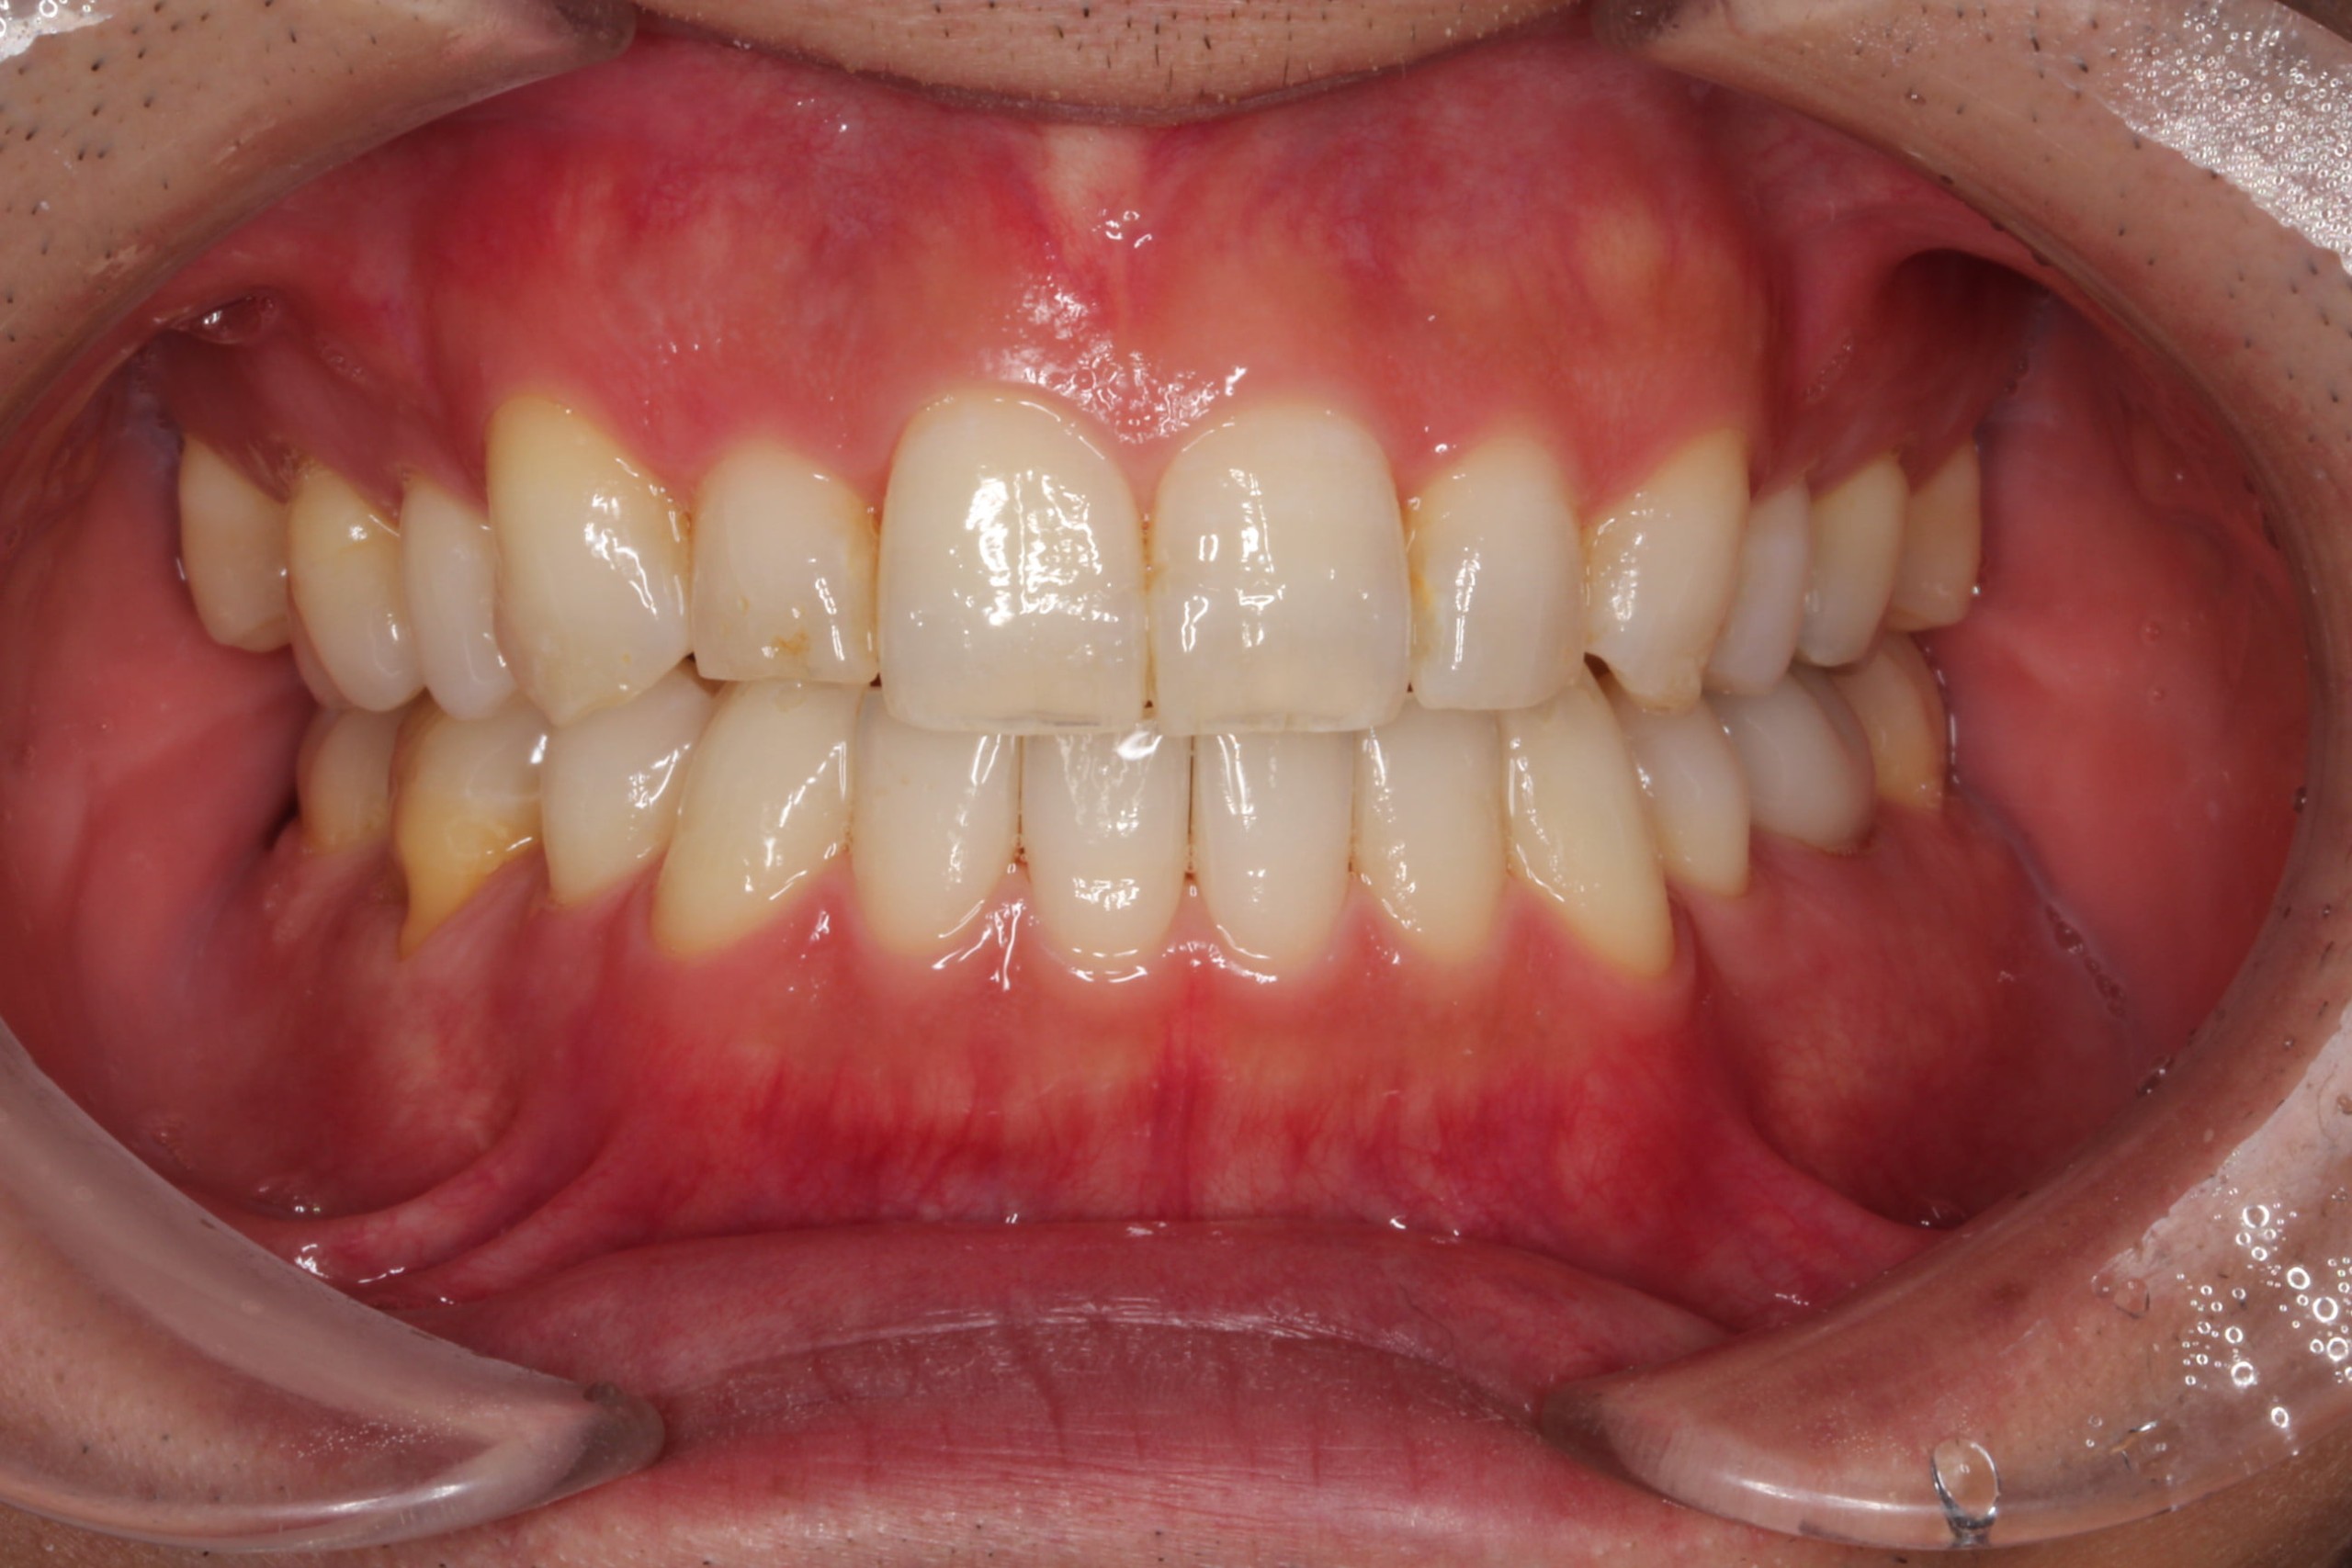

歯のデコボコを治したい

年齢層 30代

性別 男性

主訴 【主訴】歯のデコボコを治したい 【診断・症状】上下凸凹

治療費用 検査・診断:38,500-/裏側矯正治療:1,397,000-(※全て税込)

治療期間 約2年(26回)

抜歯 有(上4,4、下5,5)

矯正の装置 裏側矯正(舌側矯正)

副作用、リスク 歯肉退縮,歯根吸収,疼痛,咬合の違和感,装置の違和感,虫歯,歯肉炎

case8_デコボコ抜歯_before

Before

case8_デコボコ抜歯_after

After